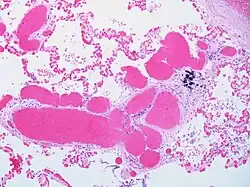

Alveolar capillary proliferation as well as proliferation of larger blood vessels, probably venules.